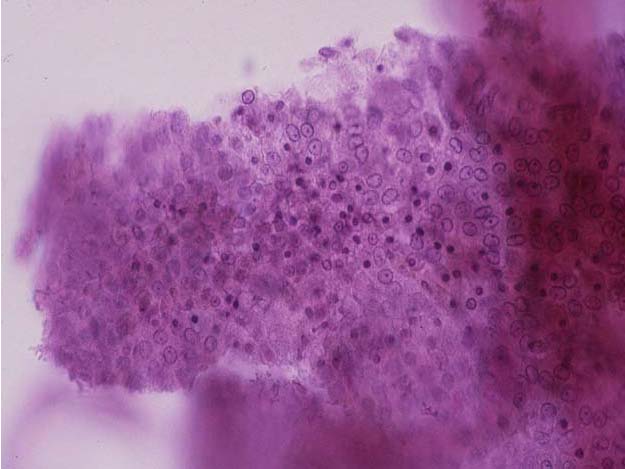

เชื้อ MBV ติดต่อโดยตรงทางการกินเนื้อเยื่อกุ้งที่ติดเชื้อ หรืออุจจาระ น้ำที่ปนเปื้อนเชื้อ กุ้งกุลาดำทุกระยะสามารถติดเชื้อได้ ยกเว้นระยะไข่ และ nauplius ไม่พบว่าติดต่อผ่านสัตว์พาหะ อาการในกุ้งวัยอ่อน (larval stages ได้แก่ ระยะ zoea และ mysis) จนถึงระยะพี (postlarva) อาจพบการตายมากกว่า 90 เปอร์เซนต์ ในขณะที่กุ้งระยะ juvenileและกุ้งโตเต็มวัย อาจติดเชื้อได้แต่ไม่ตาย อาการที่พบได้แก่ อัตราตายการสูง ไขมันในเฮปปาโตแพนเครียส (hepatopancreas) ต่ำ ลำไส้ส่วนกลาง (midgut) มีสีขาว สำหรับรอยโรคเมื่อตรวจด้วยวิธี wet mount พบ spherical occlusion bodies จาก hepatopancreas, midgut หรืออุจจาระ (รูปที่ 4) และเมื่อตรวจทาง จุลพยาธิวิทยา พบintranuclear, eosinophilic, round occlusion bodies ใน epithelial cells ของ hepatopancreas หรือในเซลล์เยื่อบุของ anterior midgut การควบคุมและป้องกัน ไม่มียารักษาโรคหรือวัคซีนป้องกัน แต่มีวิธีหลายวิธีที่อาจใช้ป้องกันโรคได้ วิธีแรกเรียกว่า “ตรวจแล้วทำลาย” ซึ่งทำในโรงเพาะฟักคือตรวจกุ้งพ่อแม่พันธุ์ โดยอาจตรวจอุจจาระ หรือ สุ่มกุ้งมาตรวจทางจุลพยาธิวิทยาซึ่งต้องฆ่ากุ้ง หากพบเชื้อไวรัสใน เฮปปาโตแพน เครียส หรืออุจจาระ ก็ให้ทำลายกุ้งนั้น (ปัจจุบันอาจตรวจด้วยวิธีพีซีอาร์) วิธีที่สองเรียกว่า “

รูปที่ 4 Occlusion bodies ของ MBV คงตัวอยู่ได้นาน 30 นาที